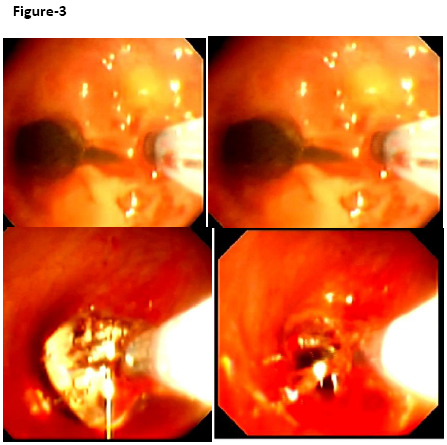

Therapeutic flexible bronchoscopy was performed under local/general anesthesia in the operation theatre. Initially, an electocautery probe was passed through the suction channel of the fibreoptic bronchoscope under 35-40% oxygen supplementation. Linear cuts were given using the “blend” mode on the electrocautery unit which allows tissue cutting and coagulation simultaneously. The electrocautery knife created 1 to 2 mm incisions at targeted points and the balloon dilated the airway. Continuous suction was applied so that the target area remained free of blood and mucus and smoke was evacuated. The linear cuts were made on the walls of the stricture at 12 o’clock, 3 o’clock and 9 o’clock position. During inflation, a balloon inflation device with pressure gauge monitor (Boston Scientific) was used to inflate the balloon (Figure-3). The balloon was initially inflated in the stenosed segment with pressure of 2–3 atm for 15 seconds, and this procedure was repeated thrice. The patient was provided 70% oxygen inhalation before and after the balloon dilatation. Later on, topical spray with mitomycin C was given to prevent re-stenosis. Check bronchoscopy after one week revealed good dilatation of subglottic stenosis.

Figure-3Incision of  stenosis at  3 o’clock  position  and  dilated with  Boston  balloon